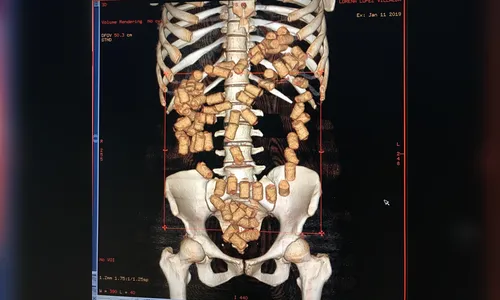

A Polícia Federal prendeu uma jovem de 23 anos nesta sexta-feira (11) no aeroporto de Foz do Iguaçu, no oeste do Paraná, com 87 cápsulas de cocaína no estômago e no intestino. Outros 300 gramas da droga estavam escondidos na vagina da mulher que tem nacionalidade paraguaia.

A paraguaia, que embarcaria para São Paulo e seguiria para Valência, na Espanha, foi levada para o Hospital Municipal de Foz do Iguaçu onde deve ficar internada para expelir a droga. Depois, ela será encaminhada para a Delegacia da PF.